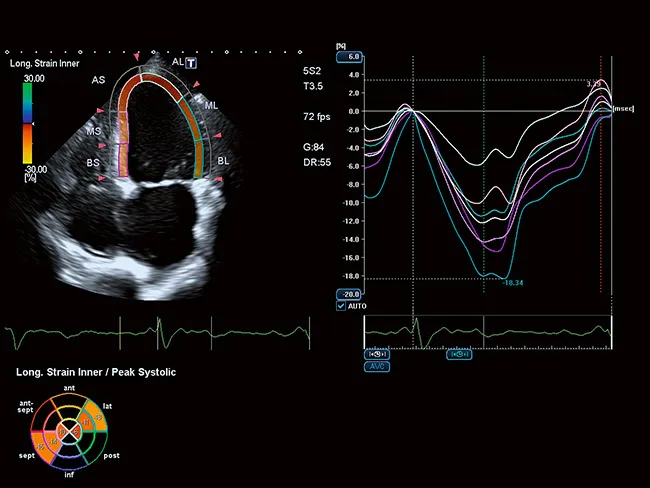

Точное количественное определение регионарной функции миокарда

Функциональная оценка лежит в основе визуализации сердечно-сосудистой системы. Предоставляя ценную дополнительную информацию в удобном для понимания визуальном, параметрическом или количественном формате, расширенные клинические функции Aplio помогут вам получить более быстрый и надежный диагностический результат.

Усовершенствованная технология отслеживания движения сердечной стенки Aplio обеспечивает немедленный визуальный и количественный доступ к глобальной и региональной статистике движения стенки миокарда.